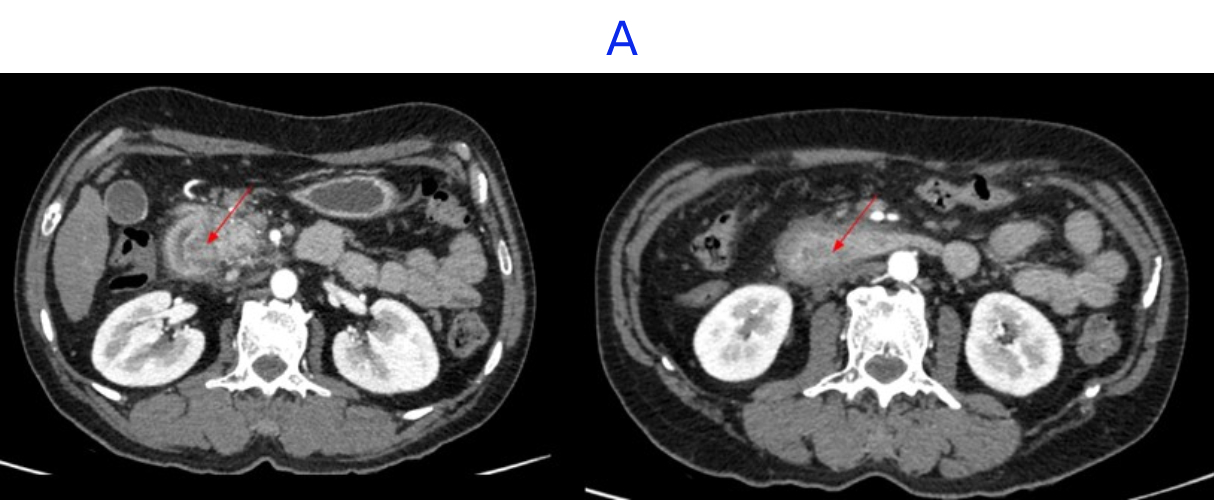

- A. Circumferential irregular submucosal wall thickening noted in D2 and D3 segment of duodenum causing luminal narrowing.

- B. Few hypoenhancing areas within the medial wall of duodenum. Uncinate process of pancreas appears oedematous.

- FDG avid heterogeneously enhancing lesion exophytic growth / thickening in D2/D3 segment of duodenum- likely malignant.

- FDG avid upper abdominal nodes.